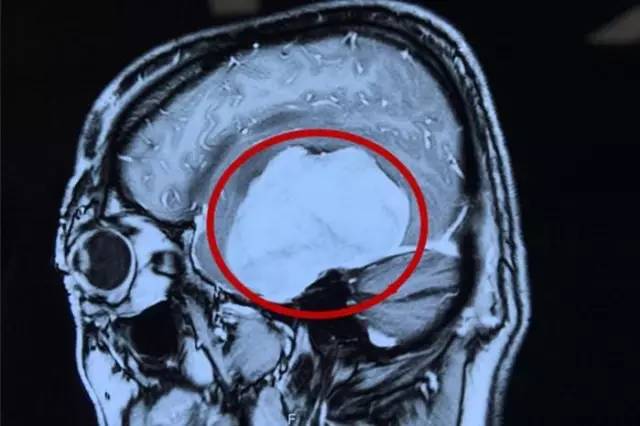

术前影像资料:红圈内白色部分为肿瘤物

术后影像资料:白色肿瘤物消失

4月23日上午8:00,一切术前准备工作完毕后,虞文军在我院DSA血管介入诊疗科接受了“超选择性全脑血管造影术+脑膜瘤供血动脉栓塞术”,对肿瘤供血动脉进行了栓塞。接着,虞文军被推入了手术室,在全麻状态下,潘仁龙主任为其实施了“左侧颞底部巨大脑膜瘤切除术”。去除骨瓣后,患者颅内压极高,见硬膜肿瘤已侵蚀,肿瘤组织质较韧,呈砂砾状。为进一步减少术中出血,将周边组织悬吊好后,薄膜内分块切除肿瘤组织、分离肿瘤包膜,肿瘤被大部切除后,上手术显微镜处理中颅离底肿瘤基底部并电烧基底面,肿瘤组织被全部切除。手术完满结束,术中出血约600ml,术后患者安返ICU重症监护室进行监护。